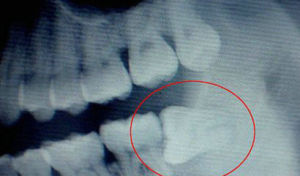

牙在頜骨內由於位置不當,不能萌出到正常咬合位置,被稱為阻生牙或阻生齒。最常見的阻生牙是下頜第三磨牙,其次是上頜第三磨牙和上頜尖牙。據統計,成人中阻生牙的發生率為20%。這種阻生牙和覆蓋在它上面的牙齦之間,很容易藏污納垢,孳生細菌,引起口臭、齲壞,當身體抵抗力下降時,常常會發生炎症。

智慧齒出血,屬於智齒阻生的一種情況